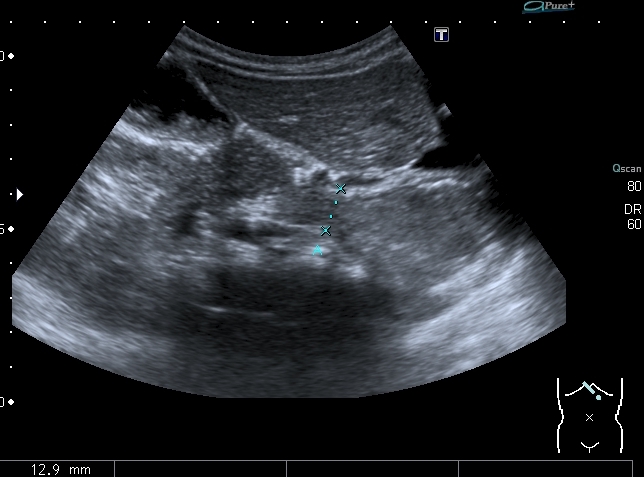

Девочка 4-х лет, жалобы на длительный кашель (оеоло 1-го месяца). В поликлинике выполнена рентгенография органов грудной клетки, выявлены изменения (какие - пока не скажу). Госпитализирована. Направлена на УЗИ сердца. При УЗИ - в самом сердце - патологии не выявлено, но позади него к правому предсердию прилежит полостное образование с акустически неоднородным содержимым.

Анализы крови - не изменены, температуры - нет. Девочка чувствует себя хорошо. Небольшая подсказка: я перешёл с секторального кардиологического датчика на абдоминальный...Serg

Сканы через пищеводное отверстие диафрагмы